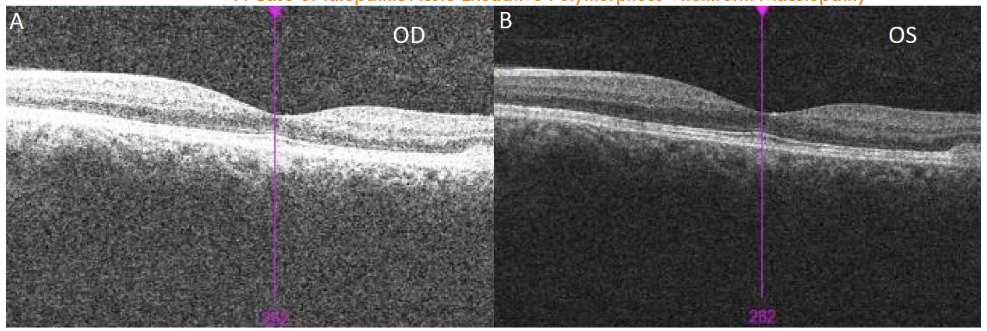

A 22-year-old male with an ocular history of amblyopia, hyperopia, and significant nicotine use presented to clinic with one week of blurry vision and headaches after moving heavy objects. On evaluation, the patient’s best corrected visual acuity (BCVA) was 20/40 in the right eye and 20/80 in the left eye. Fundoscopic exam revealed macular elevations with areas of hypopigmented demarcation inferiorly and vitelliform pseudohypopyons inferior to the fovea with few yellow flecks along the arcades. No vitritis was evident on exam. Ocular Coherence Tomography (OCT) showed subretinal fluid, intraretinal cysts, shallow neurosensory retinal detachment, and a thickened appearance to the retinal pigmented epithelium (RPE) in both eyes with vitelliform deposits inferior to the left fovea.

In terms of other tools that an ophthalmologist could use to help narrow the differential diagnoses, diagnostic imaging remains an important means of differentiating between different retinal disorders. Fundus autofluorescence (FAF) is a non-invasive diagnostic imaging tool that utilizes lipofuscin to highlight areas in the RPE where there is pathology. Given that the development of AEPVM is marked by lipofuscin overaccumulation, the intensity of the vitelliform lesions in FAF is directly correlated with the amount of lipofuscin. Ocular Coherence Tomography (OCT) is another non-invasive diagnostic imaging test that can show serous detachment, as well as other pathology, present in the macula. This modality can be used to show the extent of the serous detachment and be used to track its improvement or worsening over time. Although these can be used in many other ocular conditions, the utilization of these diagnostic imaging studies can be extremely useful in narrowing the differential diagnoses and determining the degree of the disease when regarding AEPVM.